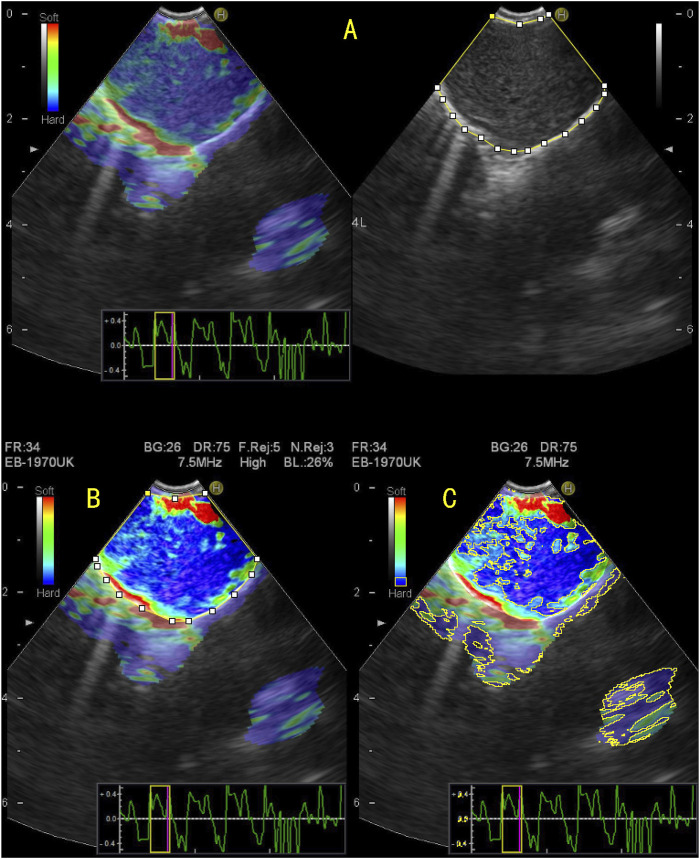

目的:在恶性肿瘤中,弹性成像和血清肿瘤标志物显示出很高的诊断效力。因此,我们旨在定量分析肺癌支气管内弹性成像结合血清肿瘤标志物的结果,以准确区分纵隔和肺门淋巴结的良恶性。研究方法回顾性收集2018年1月至2022年8月期间在我院接受支气管内超声引导下经支气管针吸术治疗纵隔淋巴结肿大的患者资料。评估定量弹性成像和血清肿瘤标志物的特征。结果:我们共收治了197名患者(273个淋巴结)。在纵隔和肺门淋巴结的良恶性鉴别诊断中,淋巴结的硬度面积比(SAR)、应变比(SR)和应变率均有显著意义,其中SAR的诊断价值最高(临界值为0.409)。四种肿瘤标记物的组合具有很高的诊断价值(AUC,0.886)。三种定量弹性成像指数与血清肿瘤标志物相结合对肺癌的诊断价值更高(AUC,0.930;敏感性,83.5%;特异性,89.3%;阳性预测值,88.1%;阴性预测值,85%)(P < 0.05)。在肺癌病理类型的鉴别诊断中,不同的肺癌定量弹性成像指标和血清肿瘤标志物对肺癌病理类型的鉴别诊断具有不同的诊断意义。结论支气管内超声弹性成像定量分析结合肿瘤标志物可提高纵隔及肺门淋巴结良恶性诊断率,有助于指导假阴性淋巴结的穿刺,降低误诊率。

Purpose: In malignant tumours, elastography and serum tumour markers have shown high diagnostic efficacy. Therefore, we aimed to quantitatively analyse the results of endobronchial elastography combined with serum tumour markers of lung cancer to accurately distinguish benign and malignant mediastinal and hilar lymph nodes. Methods: Data of patients who underwent endobronchial ultrasound-guided transbronchial needle aspiration for mediastinal lymph node enlargement in our hospital between January 2018 and August 2022 were retrospectively collected. The characteristics of quantitative elastography and serum tumour markers were evaluated. Results: We enrolled 197 patients (273 lymph nodes). In the differential diagnosis of benign and malignant mediastinal and hilar lymph nodes, the stiffness area ratio (SAR), strain ratio (SR), and strain rate in lymph nodes were significant, among which SAR had the highest diagnostic value (cut-off value, 0.409). The combination of the four tumour markers had a high diagnostic value (AUC, 0.886). Three types of quantitative elastography indices combined with serum tumour markers for lung cancer showed a higher diagnostic value (AUC, 0.930; sensitivity, 83.5%; specificity, 89.3%; positive predictive value, 88.1%; negative predictive value, 85%) (p < 0.05). In the differential diagnosis of pathological types of lung cancer, different quantitative elastography indicators and serum tumour markers for lung cancer have different diagnostic significance for the differential diagnosis of lung cancer pathological types. Conclusion: The quantitative analysis of endobronchial ultrasound elastography combined with tumour markers can improve the diagnosis rate of benign and malignant mediastinal and hilar lymph nodes, help guide the puncture of false negative lymph nodes, and reduce the misdiagnosis rate.